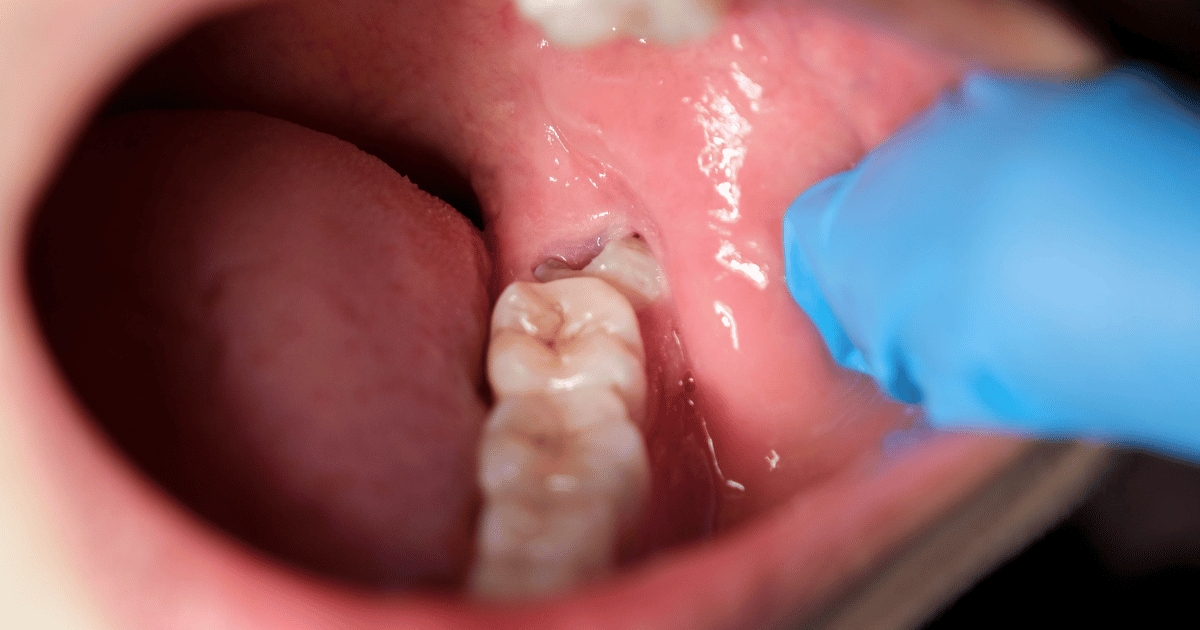

5. 抜いた箇所を舌や指で触る

触ることで細菌が入りやすくなり、感染の原因になります。違和感があっても、自然に治るまでそっとしておきましょう。